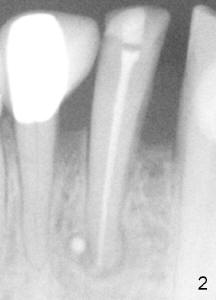

Sixty-two year old Chinese man presented to my office for new patient exam in June 2009. He has history of bruxism and wears night guard (Fig.1). The tooth #25 has incisal composite (*) with mild percussion. PAs show + PARL associated with #25 (Fig.2) and possible missing one canal (Fig.3; arrowheads point to possible 2nd root). RCT retreat was suggested. Extraction and implant were proposed as an alternative. In the next two 6-month appointments, he complained of mild pain in lower front tooth sometimes. RCT retreat was initiated on June 16, 2010. After removing composite, GP was removed with Chloroform and hand files. WL was determined by Root XZ at 15 mm. Debridement was done with hand files until #20 and rotary files until 30/.06 (Fig.4). The second canal was not found. It appears that some of GP was pushed outside of apical constriction (Fig.5 after Cavit). Twelve days later the patient returned to finish RCT retreat. It appears that symptoms improved after initiation of RCT retreat, although percussion is still mild. After removing Cavit and redebridement with #30 hand file, #10 precurved K file was inserted several times at different directions, hopefully getting into 2nd canal, which was not found. RCT filling was finished using AH Plus paste, master cone, lateral condensation with 1 medium fine accessory GP and vertical condensation (Fig.6). Composite build up was done immediately. Six months later, the patient insisted that pain is reduced substantially, but there is still mild percussion. PA shows persistent PARL (Fig.7 with outline with 2nd root (arrowheads)). Twelve months after RCT retreat, the patient is symptom-free, but objectively is not (including mild percussion and slightly enlarging PARL (Fig.8)). The 2nd canal is apparently lightly filled (red arrowhead).